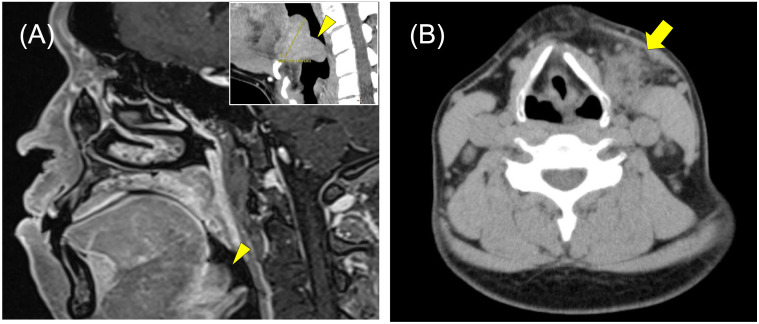

Kimura disease (KD) is a rare chronic inflammatory condition that primarily affects Asian males and typically presents in the head and neck region. We describe an exceptionally rare case of KD involving the lingual tonsil of Waldeyer's ring in a 39-year-old Japanese man, marking only the second reported instance of lingual involvement and the first specifically affecting the tongue base. The patient presented with a well-circumscribed, 3.5-cm mass extending from the lingual tonsil to the epiglottis. Laboratory findings revealed significant peripheral eosinophilia (13.5%) and elevated serum IgE levels (2,750 IU/mL). Because of the challenging location for conventional biopsy, fine-needle aspiration cytology was performed on associated cervical lymph nodes. Cytological examination identified Warthin-Finkeldey-type multinucleated cells, eosinophilic infiltration, and vascular proliferation, leading to a presumptive KD diagnosis based on cytomorphology. The diagnosis was confirmed through surgical excision and histopathological analysis. This case is noteworthy for two reasons: it documents an extremely rare presentation of KD in the tongue base and underscores the diagnostic value of cytological examination in anatomically difficult locations where surgical biopsy may be unfeasible. The presence of Warthin-Finkeldey-type multinucleated cells in cytological specimens provided a key diagnostic clue, particularly when integrated with clinical and laboratory findings. At six months post-surgery, the patient showed no recurrence. This case highlights the importance of considering KD in the differential diagnosis of head and neck masses, even in atypical locations, and demonstrates the potential utility of cytological examination in diagnosing KD.